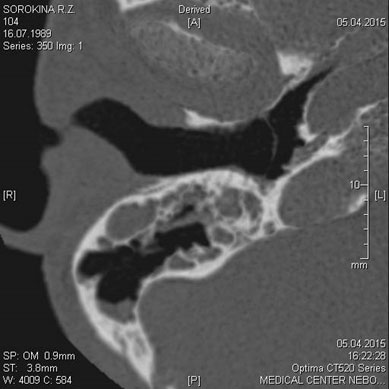

МСКТ височных костей

Показания:

- Воспалительные заболевания и их осложнения

- Травма, аномалии развития

- Опухолевый процесс